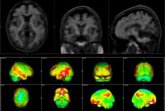

2025: El año en que la medicina ha dado un salto histórico contra el Alzheimer, el cáncer y la ELA

El año 2025 marcará un punto de inflexión en la Historia reciente de la Medicina. Desde las primeras terapias capaces de modificar la evolución del Alzheimer hasta el uso clínico de la biopsia líquida para anticiparse al cáncer, pasando por nuevos tratamientos inmunológicos en enfermedades neurológicas, y un cambio de paradigma en el manejo de la cronicidad. Así, la innovación científica ha dado pasos decisivos que ya se traducen en más supervivencia, en una mejor calidad de vida, y en una atención sanitaria más precisa.